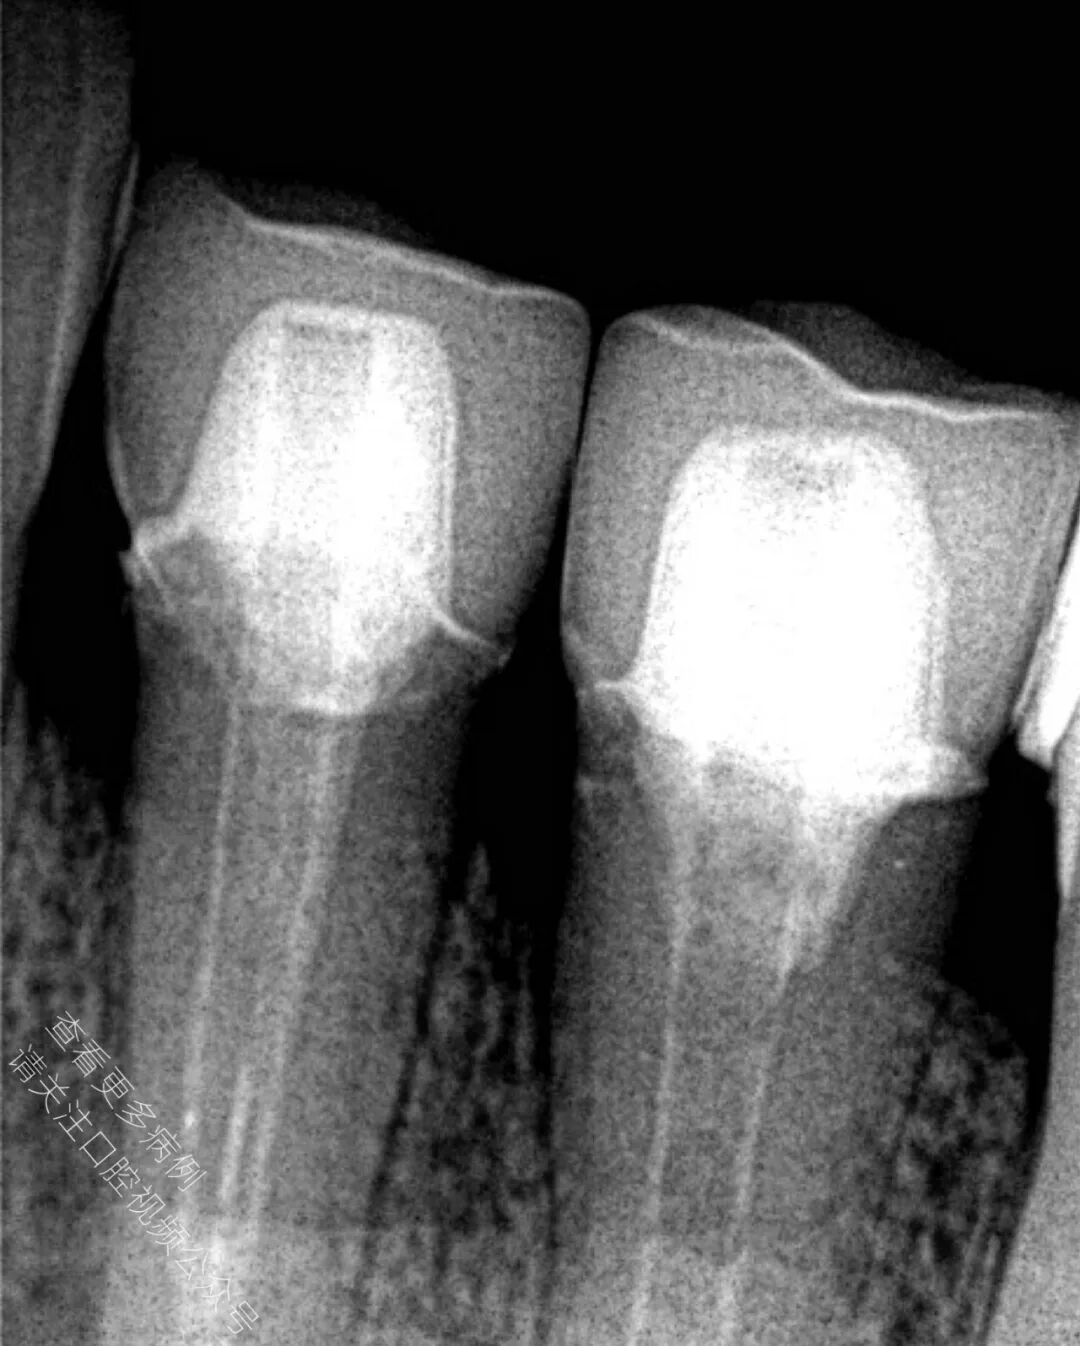

🪄 术后X光片显示冠修复体边缘密合良好,修复效果理想